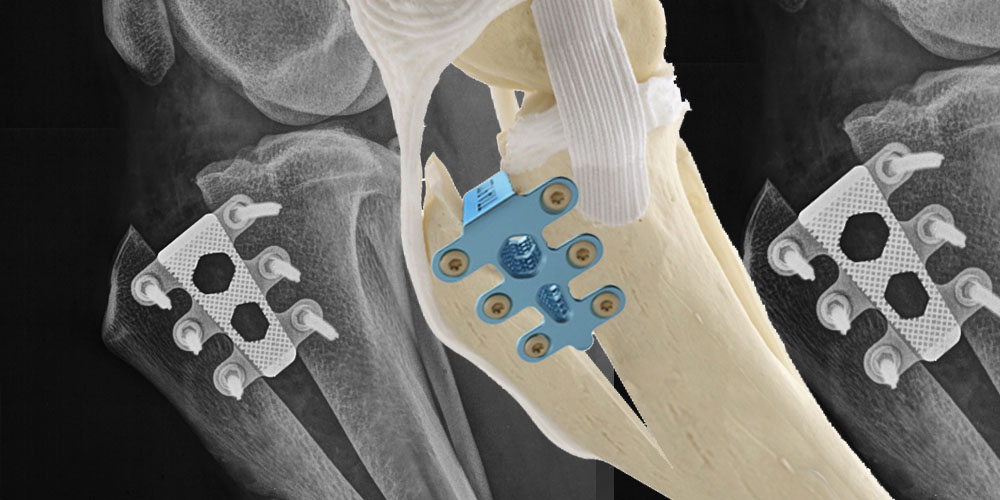

Kreuzbandriss — erkranktes Gelenk im Speziellen

Die häufigste Lahmheitsursache der Hintergliedmaße beim ausgewachsenen Hund und auch älteren Katzen ist ein Riss des vorderen Kreuzbandes, oft begleitet von einer Verletzung des inneren Meniskus. Kreuzbandrisse führen zu Instabilität, Meniskusfolgeschäden, Gelenksentzündung und Arthrosebildung im Kniegelenk. Bei einem Kreuzbandriss des Hundes liegt meist eine chronisch-degenerative Erkrankung zugrunde, weniger das scheinbar akute Trauma. Abhängig von Größe, Gewicht und Alter Ihres Tieres, sowie dem Verletzungs- und Arthrosegrad des Kniegelenkes empfehlen und führen wir die Meniskusdiagnostik und die für Ihr Tier angebrachteste Kreuzband-Operation durch. Die mit von uns weiterentwickelte, moderne TTA Rapid Methode zur Kreuzbandbehandlung mit dem Titan Implantat der Firma R.Leibinger medical bietet eine sehr frühe Wiederbelastung der operierten Gliedmaße und schnellere Genesung Ihres Hundes und Ihrer Katze.

- TTA Rapid® Tibial Tuberosity Advancement